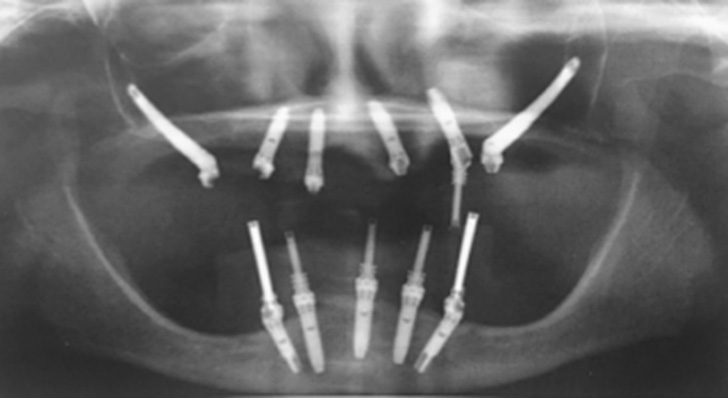

The zygomatic implants are implants that are used in case of severe maxillary atrophy.

Yes, zygomatic implants are different from standart. They are longer than and have an inclination that can range from 0 ° to 60 °.

Therefore, computed tomography and orthopantomography are required, which can allow us to assess the position of your anatomical structures. The case will then be examined and a decision will be made on which method to choose.